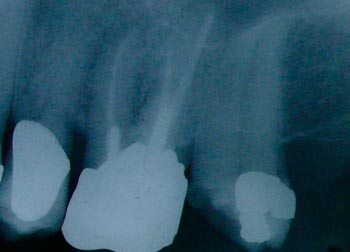

An X-ray showing 2 molar teeth with root fillingsmolar root canal

An X ray picture of an upper molar tooth with a root filling and a crownmolar root filling